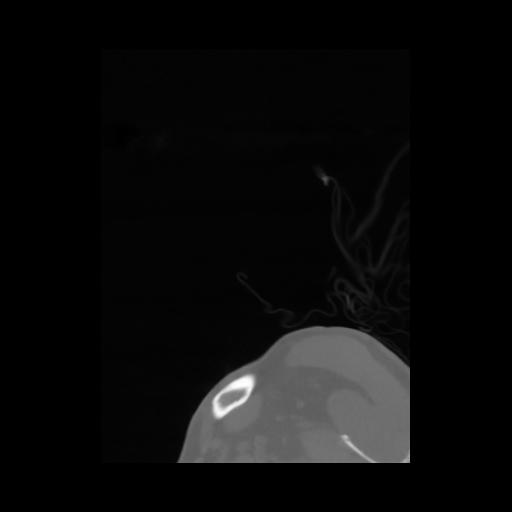

14 P.BLANDAS,,Sagittal,2.000,P.BLANDAS,Sagittal,